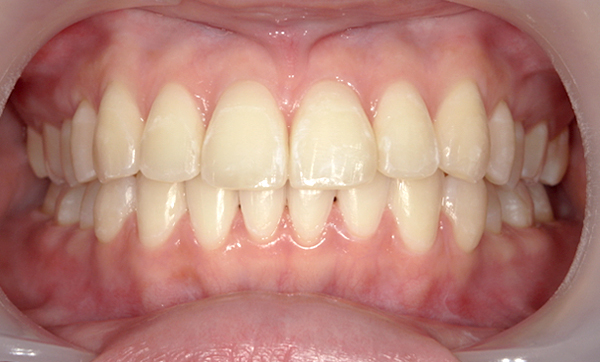

症例_009 「上下の前歯」症例

治療期間:7ヶ月金額:54万円+税20代女性捻転歯一部の反対咬合前歯のガタガタ